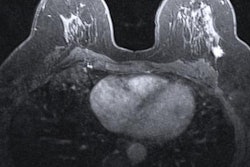

Women with triple-negative breast cancer who undergo preoperative MRI before breast-conserving surgery have lower rates of disease recurrence and reexcision, according to a study published March 18 in the Annals of Surgical Oncology.

Some consider breast MRI to be the modality with the highest sensitivity for identifying breast cancer, performing better than mammography or ultrasound -- a particular benefit for women with triple-negative breast cancer, which mammography can miss. In fact, compared with receptor-positive breast cancers, "mammography is less effective at detecting triple-negative breast cancer, with 9% to 18% showing no mammographic evidence of disease," the group wrote.